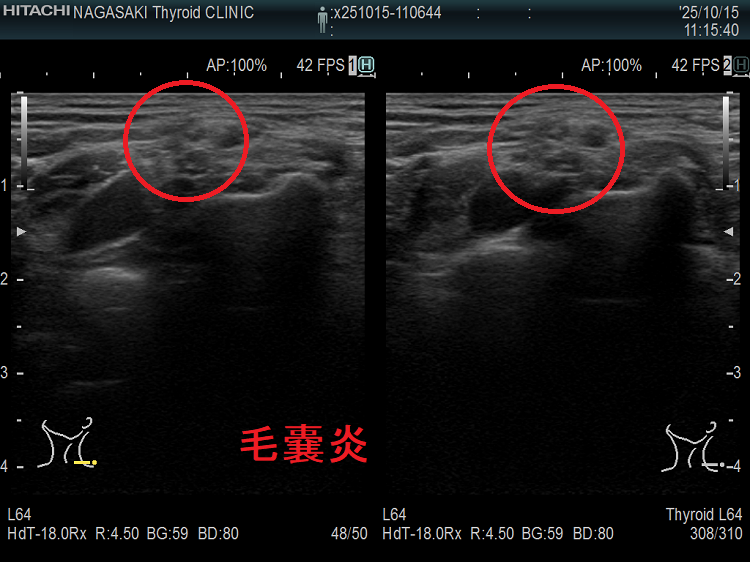

首の腫瘤・しこり・腫れに気付き、あるいは家族・友人・健康診断医・かかりつけ医に指摘され、甲状腺の病気と思って長崎甲状腺クリニック(大阪)を受診される方が大勢います。もちろん、本当に甲状腺の病気である事が多いものの、超高解像度超音波(エコー)装置で調べると、思いもよらない甲状腺以外の病気が見つかる事もあります。

このページでは、実際にあったケースを集めてみました。

首の腫瘤・しこり・腫れ、甲状腺と思っても頸部軟部腫瘍(脂肪腫・脂肪肉腫・血管脂肪腫・粉瘤・パラガングリオーマ・ユーイング肉腫・滑膜肉腫)

首の腫瘤・しこり・腫れ、甲状腺と思っても、甲状腺超音波エコー検査で見ると頸部軟部腫瘍[頚部神経線維腫・神経鞘腫・脂肪腫・脂肪肉腫(急激に増大)・筋腫・血管脂肪腫(副腎皮質ステロイドの長期間使用,糖尿病で発症。痛みを伴う)・粉瘤(アテローマ、アテローム)[皮脂がたまって腫瘍化。痛み無し]・パラガングリオーマ(傍神経節腫)(交感神経由来はカテコラミン過剰産生、副交感神経由来はホルモン産生しない)・ユーイング肉腫・滑膜肉腫]の事も。

粉瘤(アテローマ、アテローム):皮脂がたまって腫瘍化したものです。痛みはありません。

写真の様に、甲状腺の真上にあると、甲状腺腫瘤と思って、長崎甲状腺クリニック(大阪)を受診される方があります。